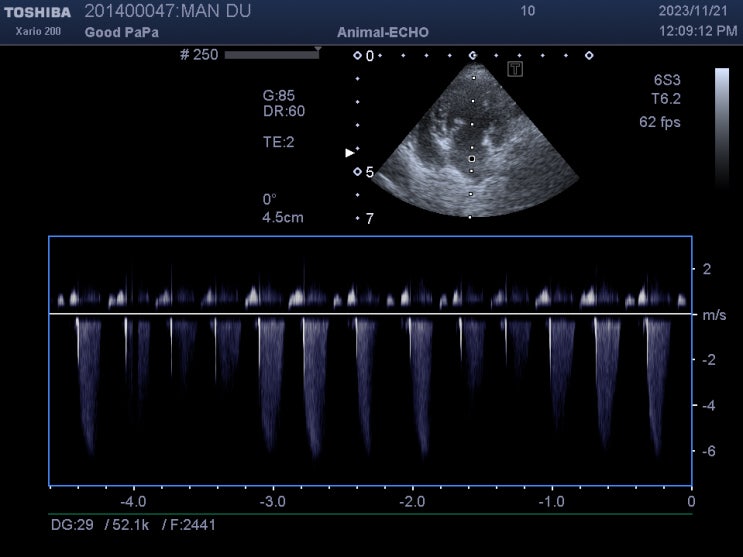

심장병 있는 8살 포메라니안 강아지 스케일링, 발치 후기 / 심장병 있는 반려견 마취하면 안 되나요? / 댕댕이 치아 부러지면 어떻게 해야 하나요? / 강아지 발치 잘하는 수의사

안녕하세요~ 굿파파 수의사입니다. 어제부터 봄비가 계속 내리네요~^^* 산과 들이 초록으로 물들어가네요~ ...